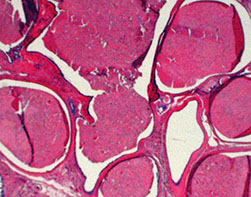

Cross section at the level of nipple shows lactiferous ducts with a scalloped appearance, possibly related to the origin of segmental branches. The duct system resembles any other dichotomously branching system of glands where a single large duct successively branches down to its most terminal level. The lactiferous duct gives rise to segmental ducts, which in turn gives rise to sub-segmental branches and so on until a terminal duct lobular unit is formed. The large lactiferous duct is the site for solitary papilloma and duct ectasia with nipple discharge.